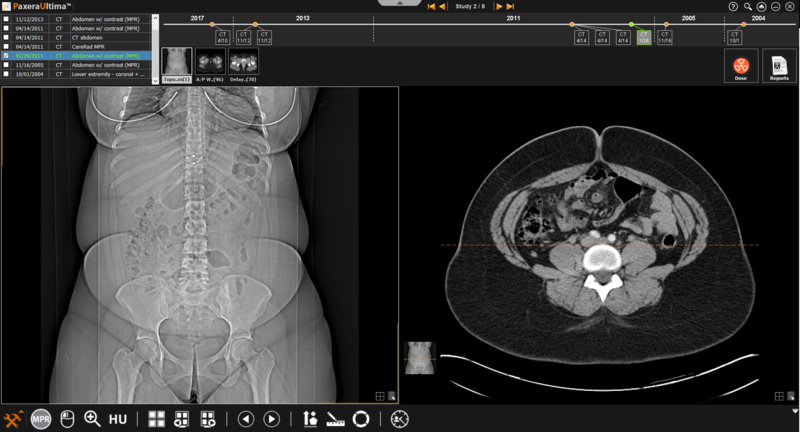

Follow the instructions below to access MRP/MIP view:

1. From the study viewer, click on the ‘Toolbox menu button located in the bottom left corner of the screen:

2. Click on the ‘MPR/MIP’ button near the bottom of the list:

3. The study viewer will change into MPR/MIP mode, an overview of this mode and along with its tools are given below: